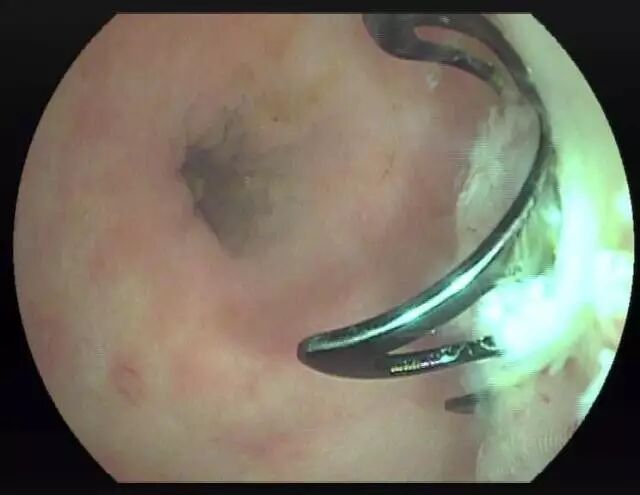

OTSC吻合夹的移除

OTSC吻合夹采用特殊合金材料,具有遇热变硬、遇冷变软的特性,释放后移除操作步骤如下:

1.将NS放在4℃冰箱内冷却

2.将4℃ NS注入OTSC吻合夹底部组织并将其浸泡1分钟

3.用抓钳抓住夹子可见部分

4.夹子此时只用很小的力量即可移除,没有见到组织撕裂伤